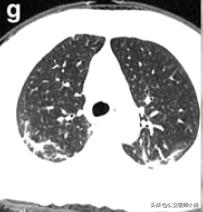

根据感染的不同程度累积一个或多个肺叶

肺部感染涉及多个肺叶-1

肺部感染涉及多个肺叶-2

肺部感染涉及多个肺叶-3

当涉及到一个或多个肺叶,肺功能的影响并不严重时,呼吸急促和呼吸困难的症状也并不严重。随着病情的发展,肺部实变开始吸收,密度降低逐渐变成毛玻璃样的混浊,像融化的糖。